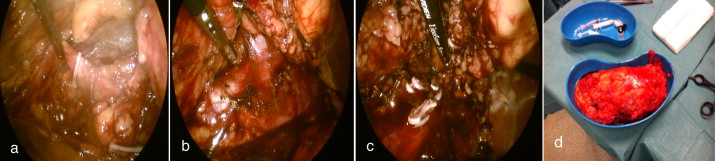

Pela aparente ressecabilidade cirúrgica, idade do doente, score do Memorial Sloan‐Kettering Cancer Center (MSKCC) e boa resposta à terapêutica com sunitinib, optou‐se pela realização da nefrectomia radical citorredutora por via laparoscópica que decorreu sem intercorrências. Na TAC de reestadiamento identificou‐se metastização pulmonar de novo e progressão de doença ganglionar e optou‐se pela reintrodução de sunitinib, 3 ciclos, 37,5 mg/dia (dosagem reduzida no contexto de hipotiroidismo). Atualmente aguarda TAC de reestadiamento, no entanto, sabemos que pela agressividade do tumor (Furhman 4) o prognóstico não é favorável fig. 4 .

Nefrectomia citorredutora laparoscópica direita. a) Laqueação do ureter, b) ...

Figura 4.

Nefrectomia citorredutora laparoscópica direita. a) Laqueação do ureter, b) isolamento da veia renal direita, c) laqueação da veia gonadal veia renal e artéria renal, d) peça de nefrectomia radical.

Anatomia patológica: CCR, células claras, Furhman 4, pT3aN2, margem hilar ocupada e restantes margens livres.